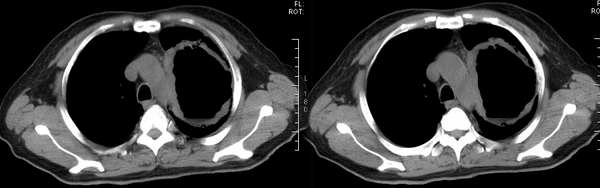

再来个空洞性肺癌,男,58岁,有咳嗽,咳痰,咯血,我看到片子时已经是治疗后复查了,第一次片子,空洞里充满了积液。